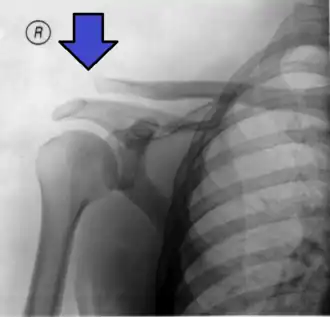

![]() Radiografía de un hombro dislocado, modificada para mostrar los huesos, apreciándose una clara separación entre el extremo de la clavícula y la escápula. | ||

La luxación o lujación de la articulación acromioclavicular es una lesión usualmente traumática de la articulación acromioclavicular (AC) donde hay daño de sus medios de unión—cápsula de la articulación y los ligamentos coracoclaviculares—con separación de las superficies articulares, donde el extremo acromial de la clavícula asciende a un nivel superior al del acromión. La articulación AC se encuentra en el extremo distal de la clavícula, se conoce como el extremo acromial, nombre que atribuye al acromion de la escápula. Aunque esta articulación es parte del hombro, una luxación y una separación son eventos completamente diferentes.